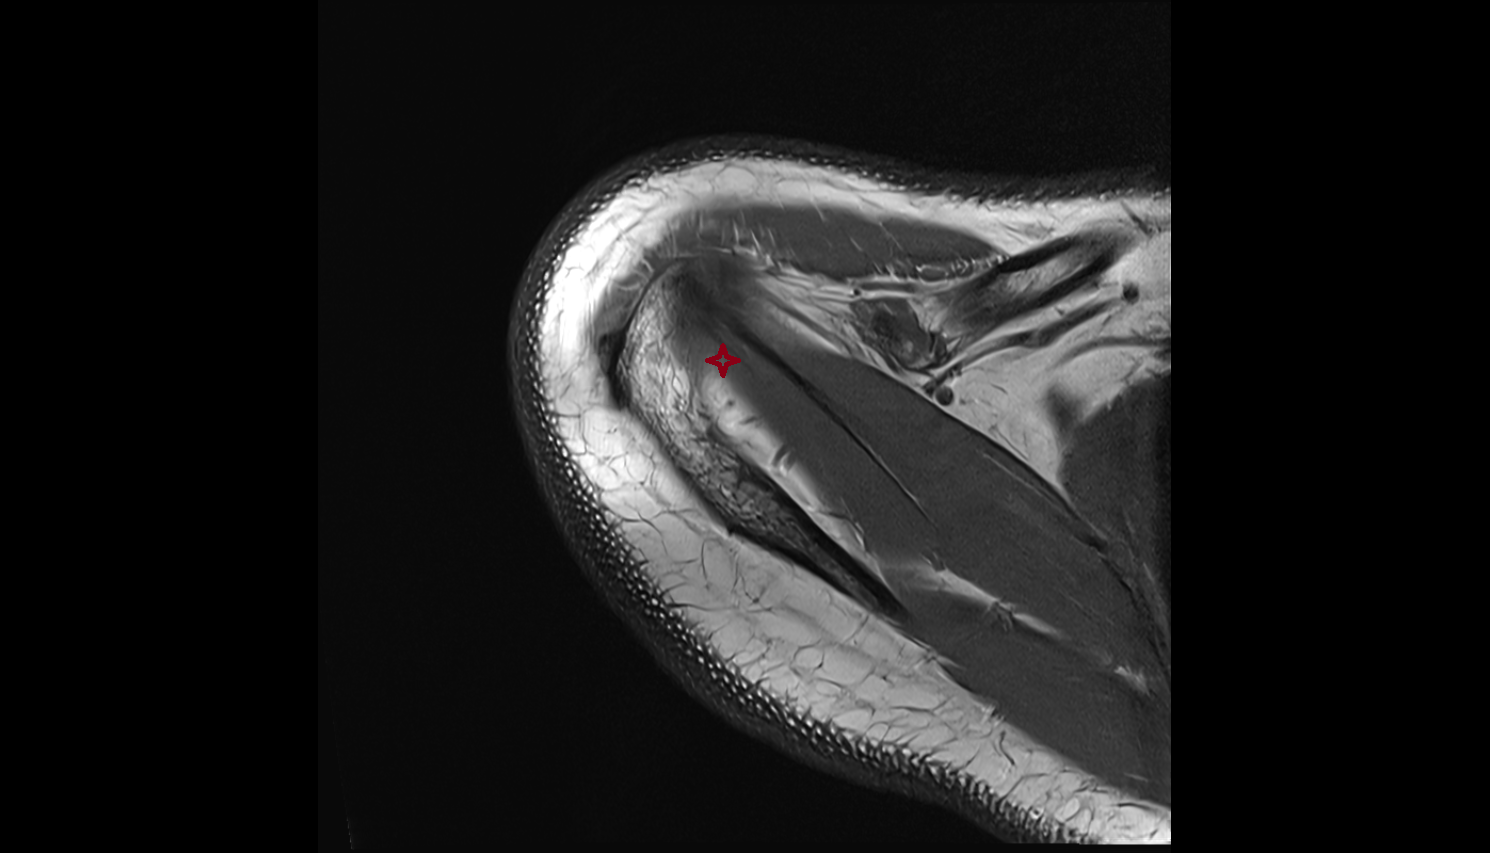

- Glenoid labrum